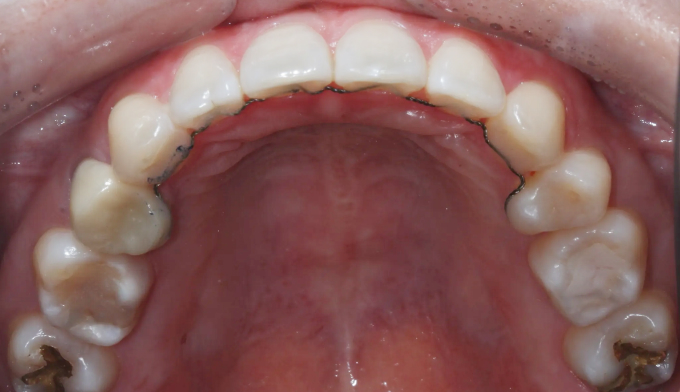

전에 교정치료를 마무리하고 지내던 중 치아 안쪽에 붙여놓은 유지장치가 떨어지면서 관리를 못하게 된 경우입니다. 이런 경우 앞니가 다시 틀어지거나 벌어질 수 있습니다.

위 유지장치는 모두 제거되어보이고, 아래 유지장치 또한 양 끝이 끊어져서 치아사이가 벌어져 보입니다.

서비스직에서 일하고 있어 치아 안쪽으로 붙이는 설측교정을 원하였고, 9개월만에 교정치료 종료 하였습니다.

유지장치가 떨어지면서 벌어진 치아들과 깊어진 앞니들을 이상적인 위치로 배열시켰습니다.